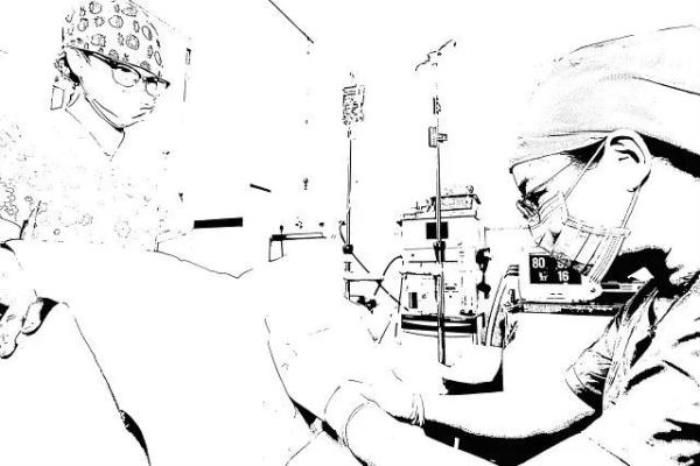

通常无痛分娩是在医护人员和产妇经过协商后决定的,需要麻醉医生、产科医生、助产士及产妇本人的共同配合。一般情况下麻醉医生在10分钟左右即可完成操作,这一过程及之后的一段时间内,医生会在产妇身旁监护其生命体征及胎儿情况,以便有异常发生时及时处理。